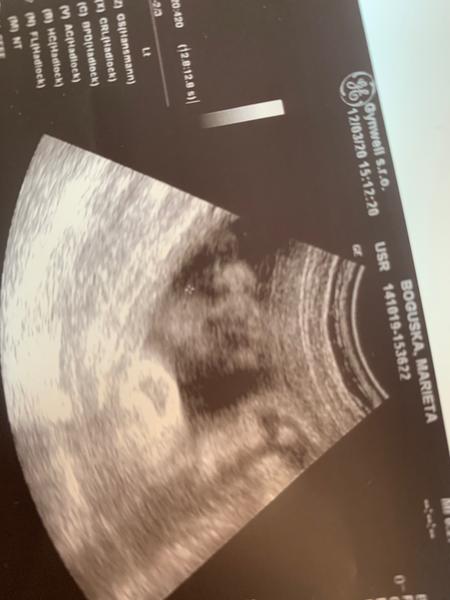

Velký nos na ultrazvuku. Máte zkušenost? A byl pak normální?

Ahoj, mám nevšední dotaz. Měli vaše miminka na fotkách z ultrazvuku velký nos a ve skutečnosti pak byl normální? Vím že mohou být ty ultrazvukové fotky zkreslené... Ano důležitější je, že je mimčo zdravé ❤️ jen mě to zajímá.

nam doktor rikal, ze pokud ma mlade na tom 3d ultrazvuku velkej nos, tak je to tim, ze pri snimani zaklonilo hlavu 🙂 ze maj jinak vsechny pidiknoflik

Mají často nos přimáčknutý, takže všelijaké patvary. Většina mimin má pidiknoflíčky pršáčky, konečný tvar se formuje po 3 letech.

Dcera měla na jednom utz místo nosu pěkný frňák a po narození po něm nebylo ani vidu. Má krásný nosík, tak se neboj. Utz muže zkreslovat ;)